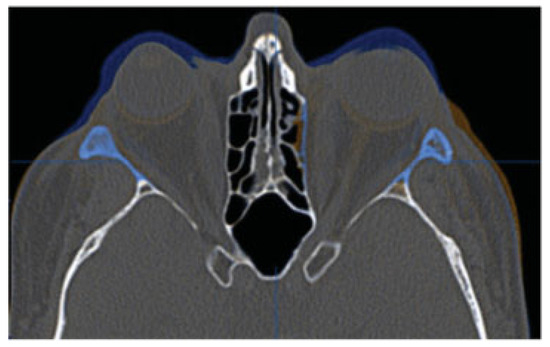

Computer-Assisted Three-Dimensional Planning for Orbital Decompression

by Nicholas Mahoney, Michael P. Grant, Srinivas Murthy Susarla and Shannath Merbs

Craniomaxillofac. Trauma Reconstr. 2015, 8(3), 211-217; https://doi.org/10.1055/s-0034-1393731 - 14 Nov 2014

Thyroid-associated orbitopathy is the most common cause of unilateral or bilateral proptosis in adults. A mainstay of surgical treatment is orbital decompression utilizing osteotomies to increase the size of the affected bony orbit to accommodate the larger soft tissue volume. Over the past [...] Read more.

Thyroid-associated orbitopathy is the most common cause of unilateral or bilateral proptosis in adults. A mainstay of surgical treatment is orbital decompression utilizing osteotomies to increase the size of the affected bony orbit to accommodate the larger soft tissue volume. Over the past several decades, numerous approaches have been described for orbital decompression. However, given the intricate osseous and soft tissue anatomy within the orbit, orbital decompression is a potentially hazardous intervention. With advances in three-dimensional imaging and virtual planning, extensive orbital decompressions can be performed safely and efficiently. In this report, we describe two cases of three-wall orbital decompressions using three-dimensional planning. Full article